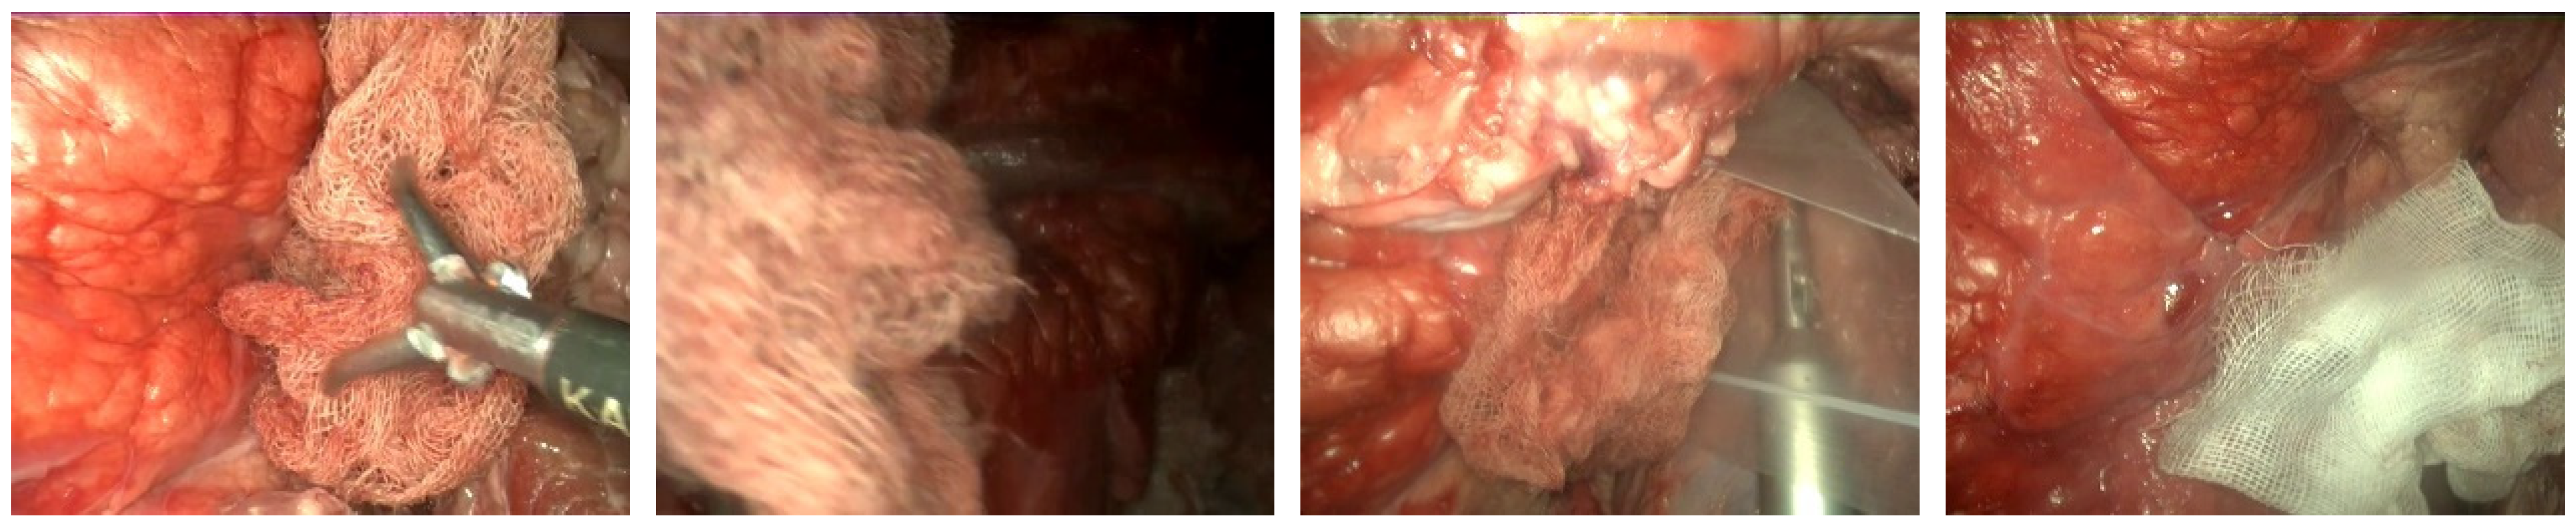

2.1. Dataset